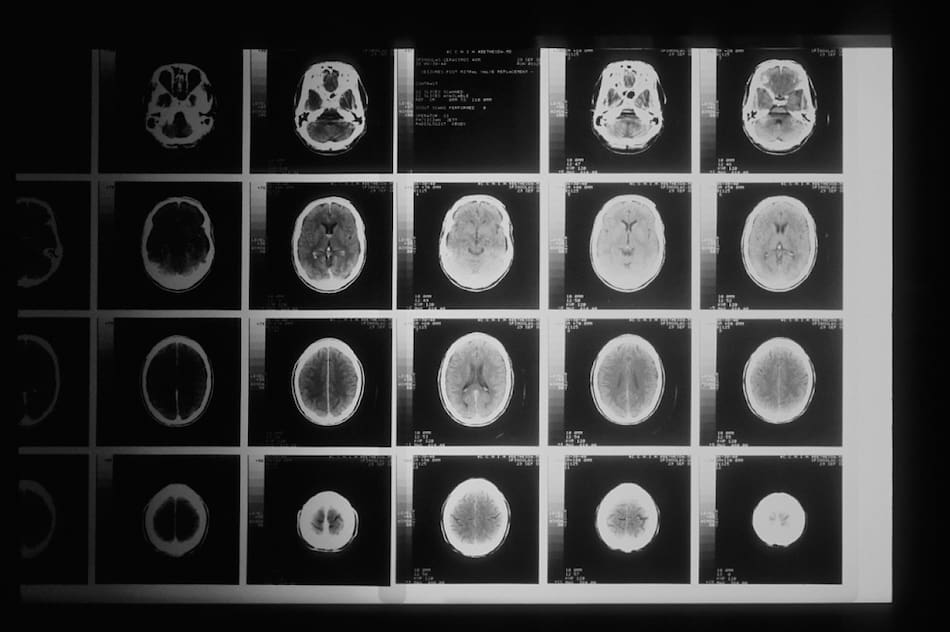

Este hallazgo permitirá nuevos tratamientos si se puede seguir profundizando su estudio. Foto: Unsplash.

Clasificar cada capa del tumor cerebral ayudaría a intentar nuevas curas de esta letal enfermedad. Foto: Unsplash.

Con estos avances podrían darse nuevos métodos de diagnóstico para los tumores cerebrales. Foto: Unsplash.